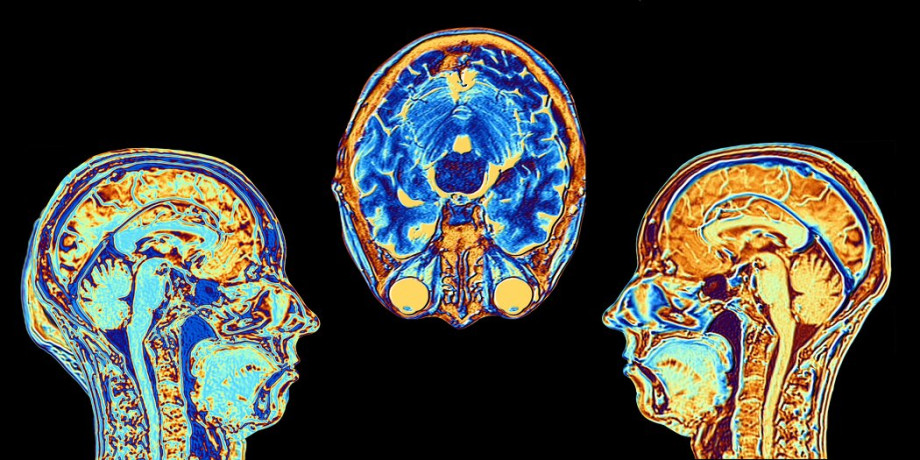

Исследования фМРТ показывают:

- При вытеснении активируется префронтальная кора (подавление) и снижается активность миндалины (эмоции)

- Отрицание связано с работой правого полушария, отвечающего за глобальное, целостное восприятие

- Проекция активирует сети, отвечающие за теорию сознания (понимание других)